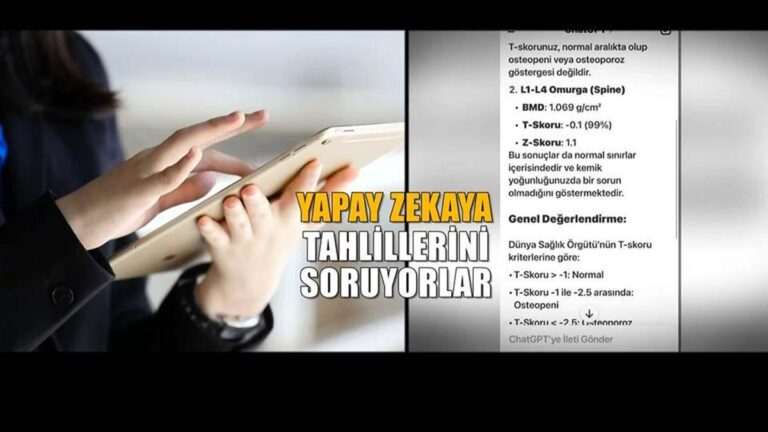

Şimdi Dr. Yapay Zeka Tehlikesi: Hatta ondan analiz istiyorlar! – Sağlık Haberleri